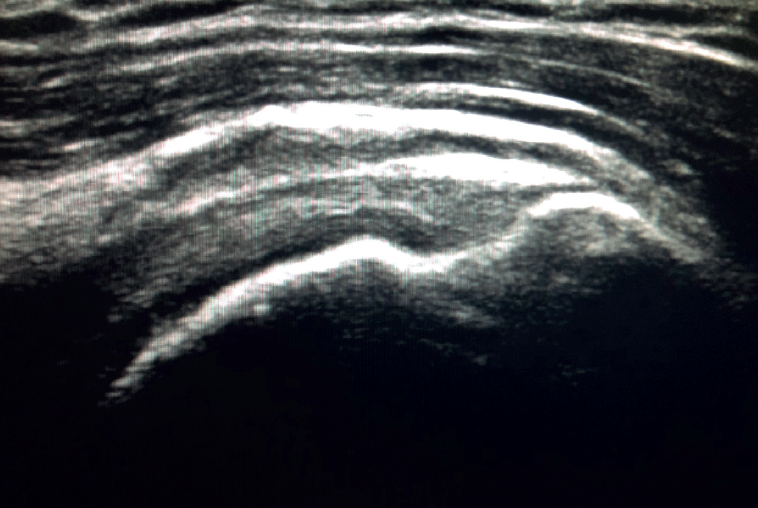

Figure 2. Ultrasound view of the long axis of the tendon of the supraspinatus muscle.

To ensure good ultrasound assessment of the posterosuperior cuff (Figure 2), we instruct the patient to place his or her arm behind the back, with the hand trying to touch the lower vertex of the scapula (Crass position). If the patient is unable to reach or keep this position during the exploration, he or she should be instructed to place the palm of the hand on the ipsilateral anterosuperior iliac crest with the elbow flexed (modification of the Crass position or Middleton position)(25). It is important to explore the tendon to its most anterior margin, as this is a frequent location of symptomatic lesions. For this purpose, in some cases the elbow must be displaced backwards, eliminating the last degrees of internal rotation.